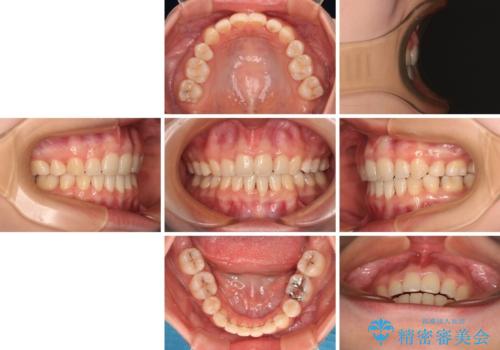

舌の突出癖の影響もあり、非抜歯矯正で治療開始したものの口元が突出し、唇が閉じにくくなってしまったため、途中で第一小臼歯4本を抜歯ししました。

口元の突出感のない、すっきりとした仕上がりとなりました。